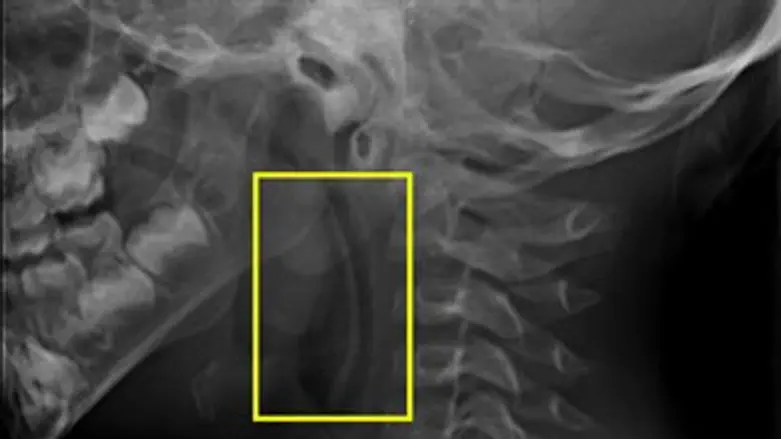

בחדר המיון קיבל את אהוד ד"ר דרור אשכנזי מומחה בכיר לאף אוזן וגרון שקבע כי יש לנתח את אהוד בדחיפות. "היה לי ברור כי ראש הכפית תקוע באזור הלוע העליון של אהוד ואכן הרנטגן אישש את חשדותיי. כמובן שמדובר במצב מסכן חיים", סיפר ד"ר אשכנזי.